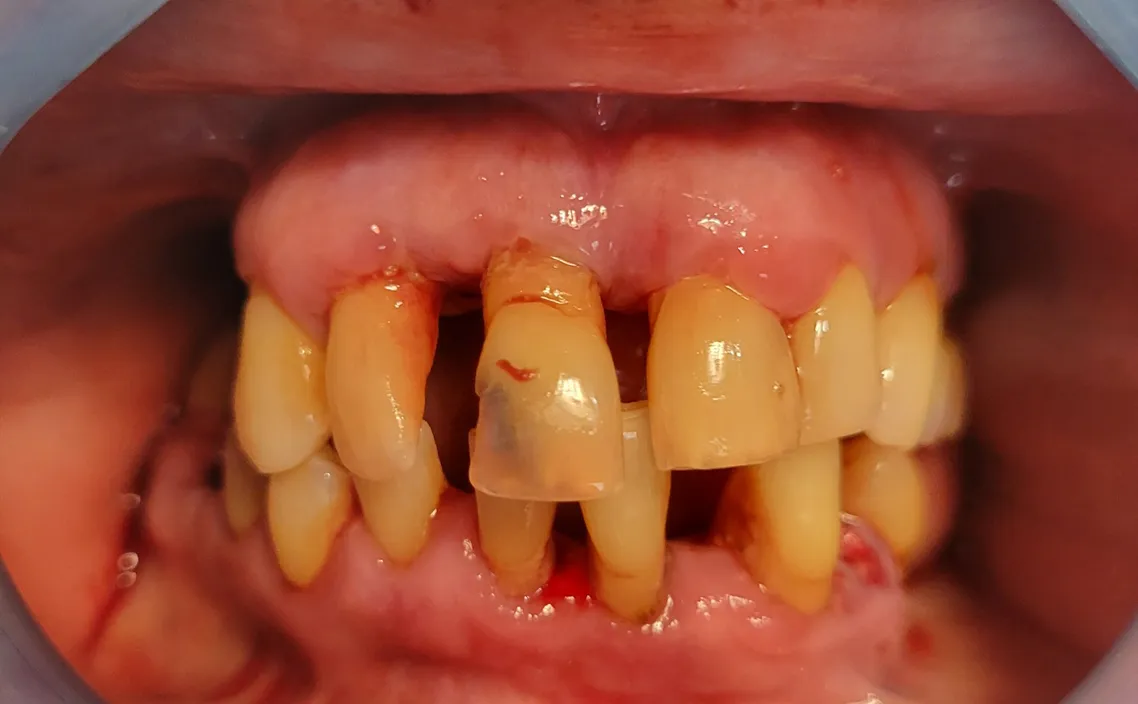

The All-on-Denture treatment is a cutting-edge solution for patients missing most or all of their teeth. Instead of traditional removable dentures, this procedure secures a full arch of replacement teeth using as few as four precisely placed dental implants. With advanced imaging like CBCT scanning and Dr. Lisa Siddall’s expert planning, the implants are positioned to maximize bone support. A custom-designed denture is then securely attached, giving you a natural-looking, fixed smile that restores your ability to chew, speak, and live confidently — all without the slipping or discomfort of conventional dentures.